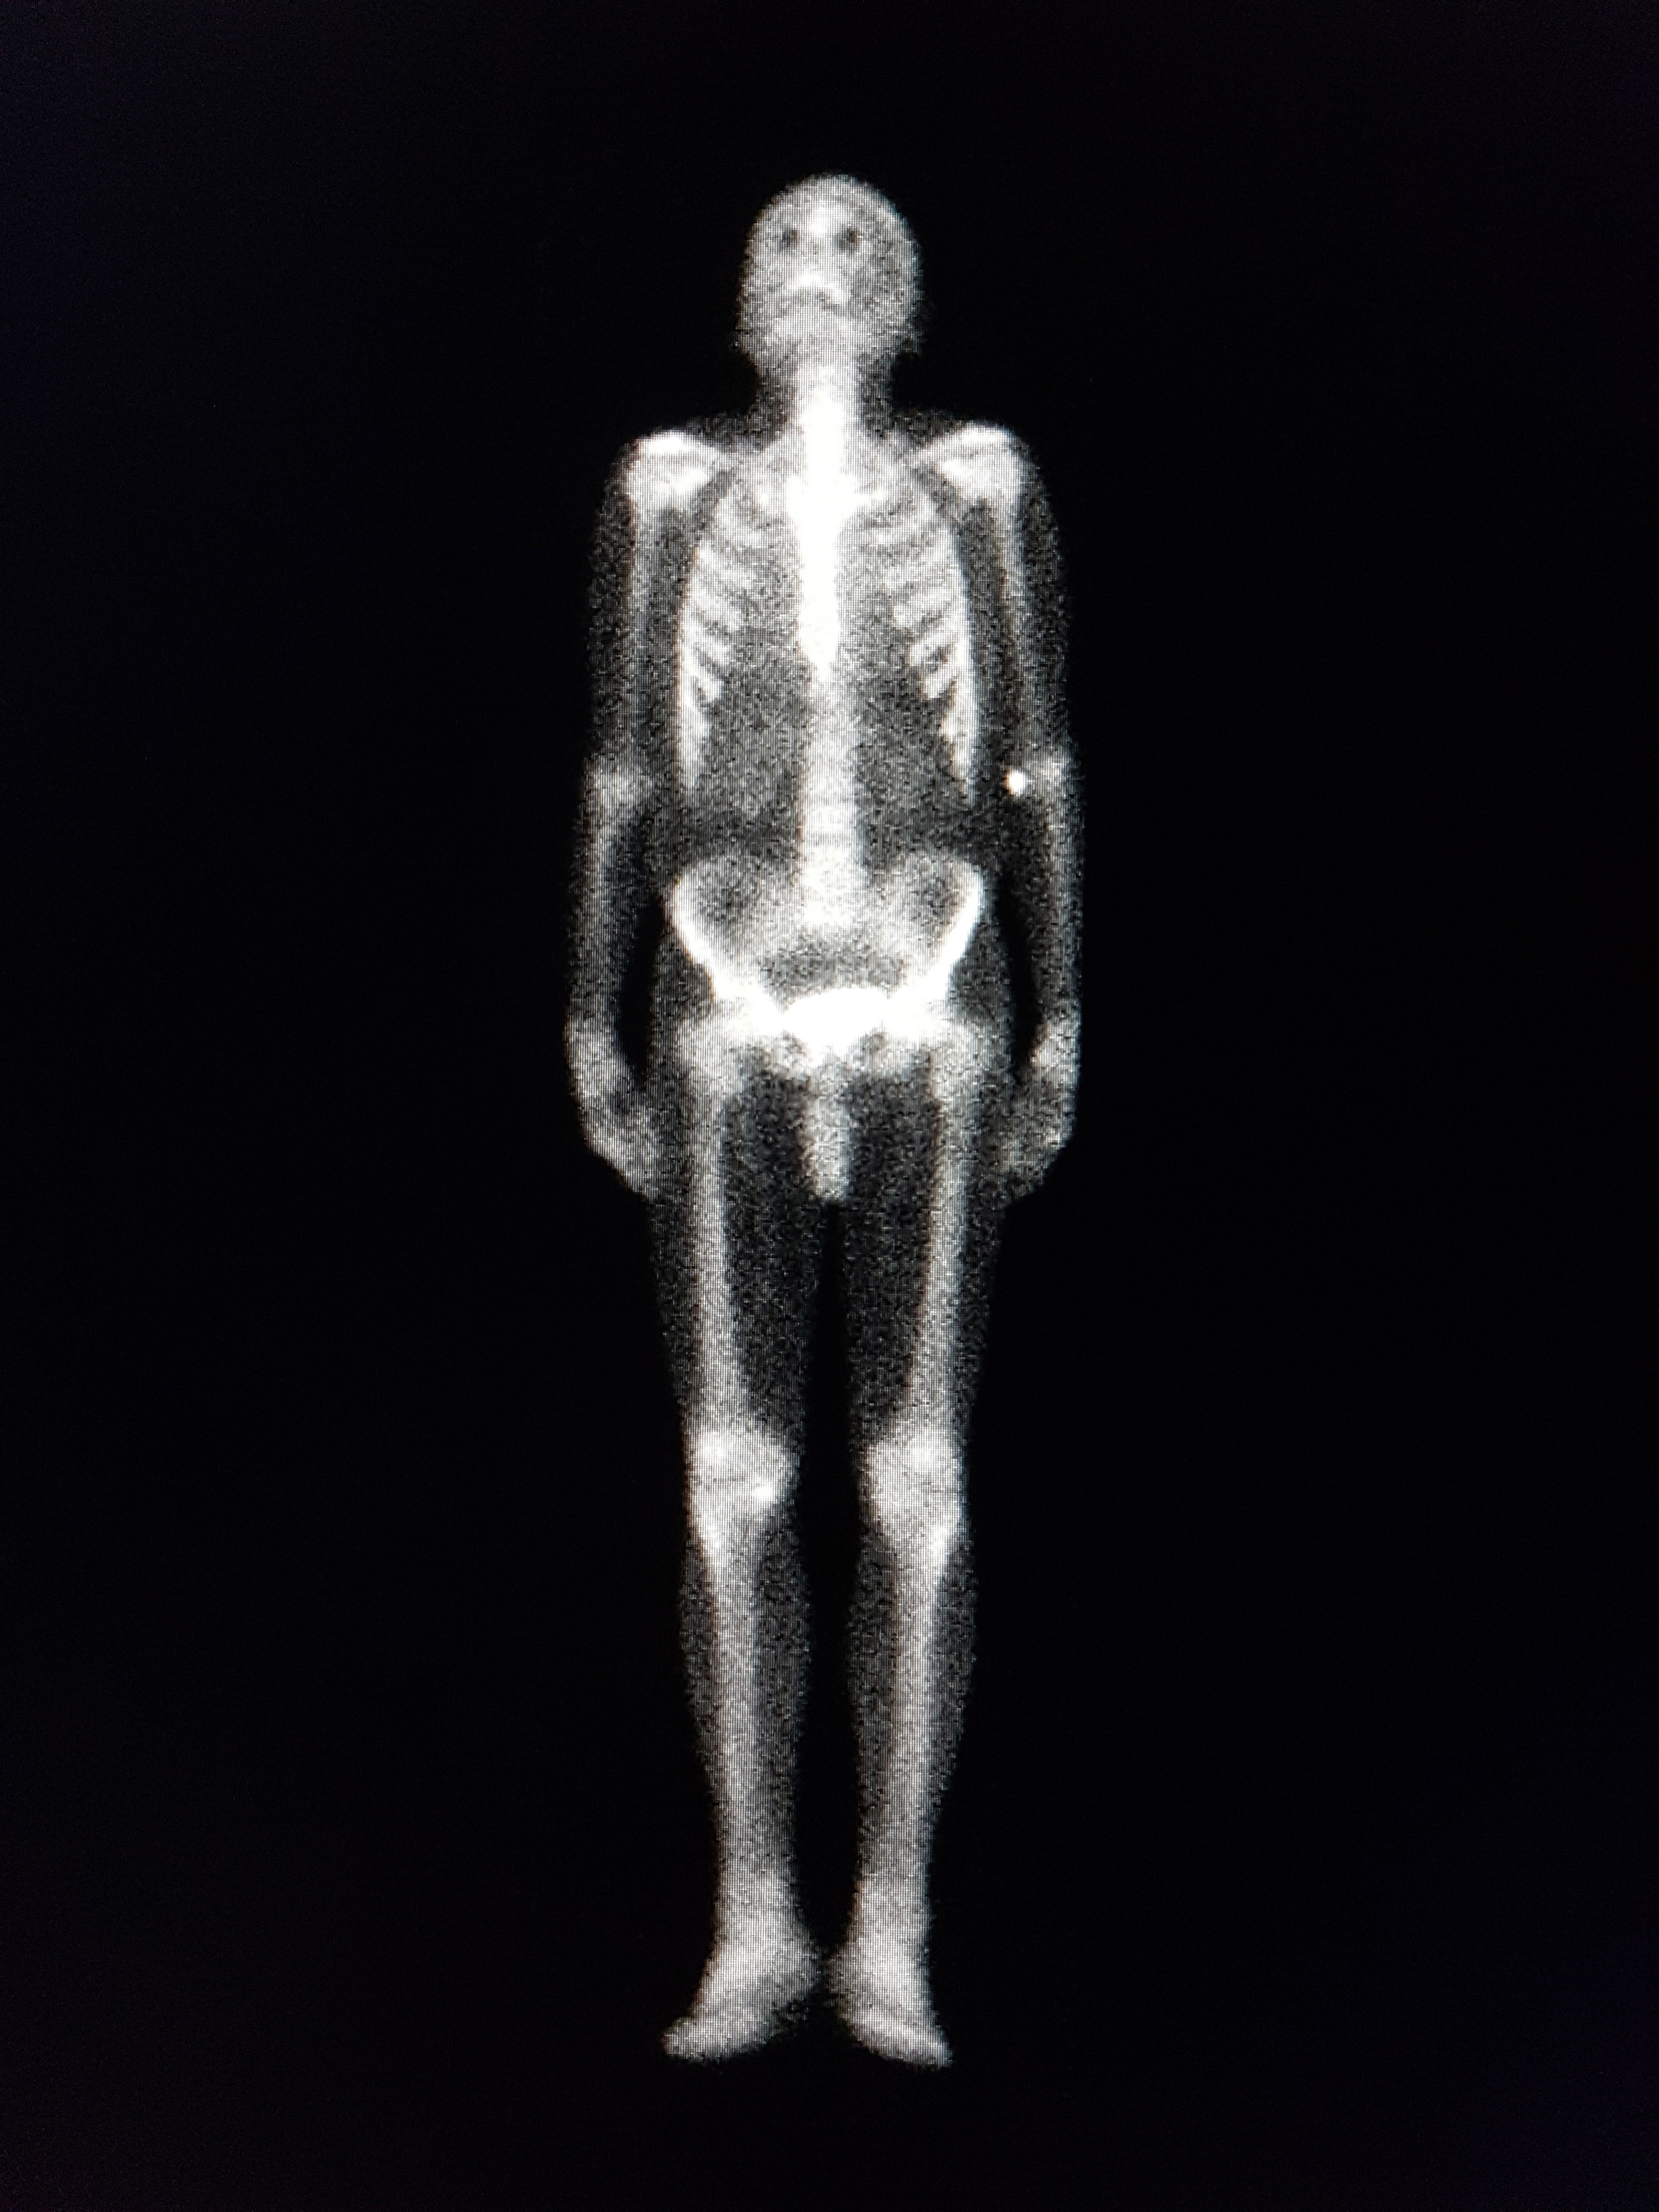

Amyloid bone scintigraphy is performed after intravenous injection of approximately 700 MBq 99 mTc-DPD/HMDP. Three hours after injection, a 20-minute whole body scan is performed. In case of cardiac uptake, proceeding with a SPECT/CT of the heart is recommended in order to characterise the localisation and distribution. Uptake of radiotracers is scored as described by Perugini (3). A positive amyloidosis bone scintigraphy (Perugini grade > 1) has > 98 % positive predictive value and specificity for transthyretin cardiac amyloidosis, provided that light chain amyloidosis is ruled out (1). If there is any evidence of monoclonal components and/or a pathologic kappa/lambda ratio, independent of Perugini score, light chain amyloidosis should be suspected (1).